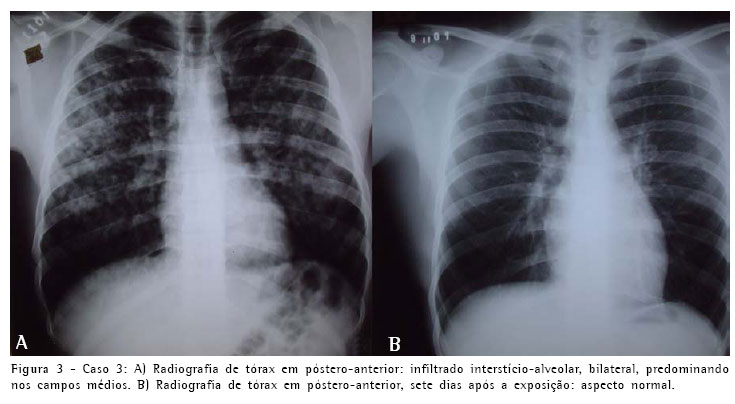

O outro paciente era um homem branco, de 19 anos, também residente em Goiânia, auxiliar de produção, que estava trabalhando junto com os outros pacientes, e que foi submetido à exposição ambiental concomitante pelo período de uma hora. Procurou atendimento de emergência no mesmo hospital, acompanhado pelo paciente primeiramente relatado. Queixava-se de dispnéia que se iniciou durante a exposição, com piora progressiva, associada a tosse seca intensa. Este paciente não referia sintomas relacionados ao sistema digestivo ou irritação de mucosa ocular ou nasal. Previamente hígido, negava tabagismo ou qualquer enfermidade importante e não fazia uso de medicação de rotina. Não tinha antecedentes de doenças familiares dignos de nota. Na admissão estava em bom estado geral, taquipnéico, cianótico +/4, com murmúrio vesicular fisiológico com estertores finos difusos. Os demais órgãos ou sistemas apresentavam-se sem alterações. A saturação periférica de oxigênio em ar ambiente era de 84%. A radiografia simples de tórax, de modo semelhante ao dos pacientes anteriores, mostrava infiltradoalveolar difuso e com áreas de confluência (Figura 3). O paciente foi hospitalizado em outro hospital da rede do Sistema Único de Saúde, por cinco dias, onde recebeu gatifloxacina na dose de 500 mg/dia, não tendo sido tratado com corticosteróides. Apresentou melhora clínica, e recebeu alta assintomático. Retornou ao Hospital das Clínicas da Universidade Federal de Goiás para acompanhamento ambulatorial oito dias após a exposição, quando realizou radiografia de tórax, espirometria, gasometria arterial e teste de difusão do monóxido de carbono, que apresentaram resultados normais.

O quadro clínico e radiológico dos três pacientes foi compatível com edema pulmonar e insuficiência respiratória aguda. A evolução revelou-se favorável e no seguimento clínico, radiológico (Figuras 1, 2 e 3) e de função pulmonar por dezoito meses não apresentaram nenhuma repercussão respiratória.

O quadro clínico e radiológico dos três pacientes foi compatível com edema pulmonar e insuficiência respiratória aguda. A evolução revelou-se favorável e no seguimento clínico, radiológico e de função pulmonar por dezoito meses, não apresentaram nenhuma repercussão respiratória.